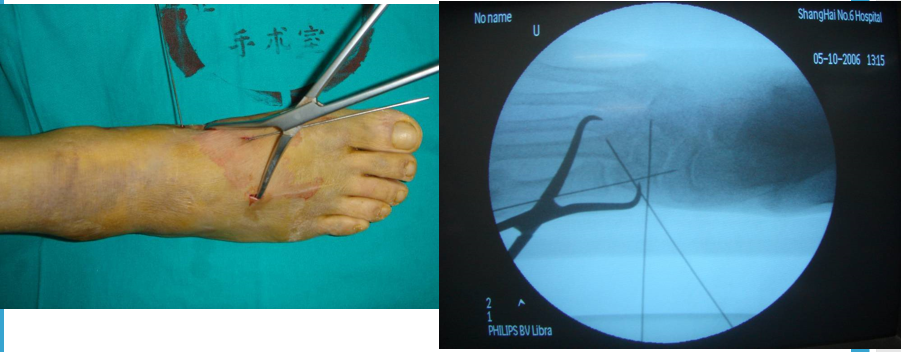

手术切口选择单一切口、双切口

双切口能充分显露所有的跖跗关节;第一切口位于第一、二跖骨之间。该切口利用了两个间隙,一个拇长伸肌腱内侧,一个为拇短伸肌腱外侧。分别可显露第一跖骨、内侧楔骨和第二跖骨、中间楔骨。通过延长皮肤切口,可以直视第三跖骨和外侧楔骨。第二切口位于第四、五跖骨之间,可以显露其与骰骨之间的关节。

根据三柱理论1、首先复位内侧柱并临时固定 2、再复位固定中间柱3、如外侧柱移位可能需双切口

手术从第一跖骨和内侧楔骨开始。首先直视下复位该关节,评价楔骨之间的稳定性,关节囊通常撕裂,但仍然需要掀开以充分显露关节,清除关节内的软组织和软骨碎片内侧柱稳定后,开始处理第二跖骨和中间楔骨。点式复位钳由第二跖骨基底部外侧远端斜向内侧楔骨内侧面的近端夹持,注意避免第二跖骨向下移位,发生复位不良。

若楔间关节仍不稳,可使用楔骨间螺钉;固定内侧两跖骨后,通常第三跖骨已经足够稳定,若仍未复位,可以参考第一跖骨固定方法固定。通过第二切口固定第4、5跖骨。可以使用克氏针固定。

Lisfranc损伤骨折复位标准:1、C形臂透视显示正、侧、斜位均为正常解剖复位2、如复位后第1、2跖骨基底间隙和内、中楔骨间隙<2mm,跖跗骨轴线<15°为近解剖复位,可以接受,超过这个范围的移位则无法接受3、复位好后,沿第一跖骨轴线向内侧楔骨逆行拧入一枚4.0mm皮质骨螺钉。螺钉由关节远侧1.5-2.0cm处进入,平行于足底或略向跖侧。

4、从内侧楔骨向第二跖骨置入一枚螺钉,重建韧带。螺钉自内侧楔骨近端的背侧置入,指向第二跖骨背侧皮质的下方,螺钉应通过4层皮质,确保对第二跖骨的双皮质固定